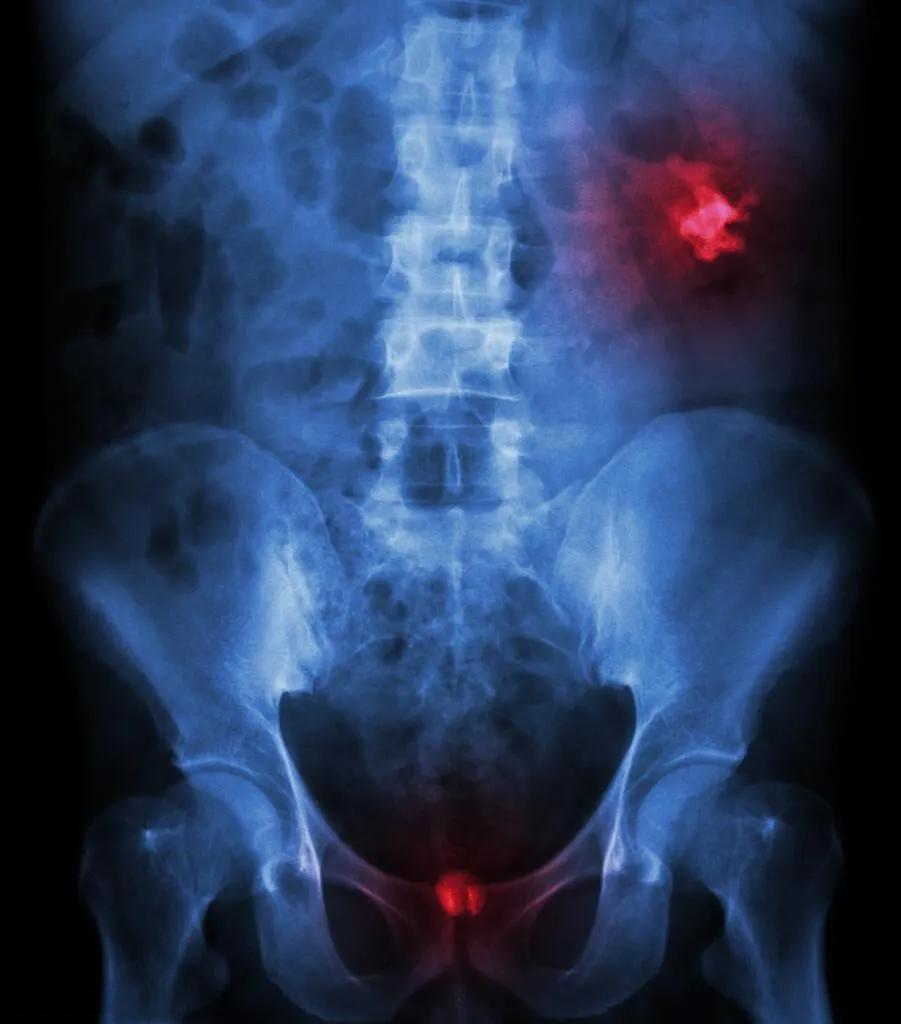

泌尿系结石的防治,主治医生都没告诉你的小知识

泌尿系结石是一种常见病,但很多人对其形成原因和预防方法并不了解。事实上,除了常规的医疗干预,还有一些鲜为人知的小知识可以帮助我们更好地预防和应对这种疾病。